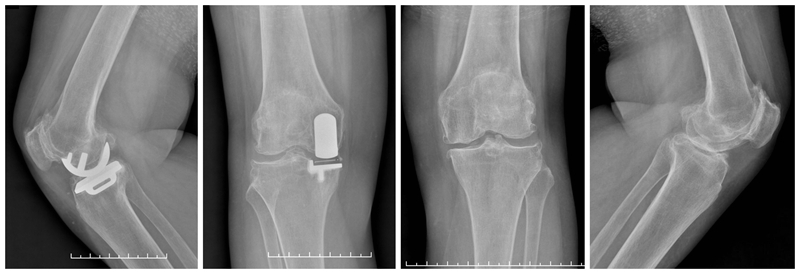

经典内侧单髁置换术(骨水泥型)

术前

术后检查

牛津单髁置换手术最经典的适应证是前内侧膝骨关节炎(AMOA),并且其他结构在功能上应保持完整,尤其强调韧带功能正常。在准备胫骨平台时,应保持7°后倾,截骨位置选在硬化骨下方,磨损最低点下方2mm处,近端紧贴,远端距皮缘18-20mm。试模间隙理想厚度6-7mm(包括胫骨假体3mm+垫片厚度3-4mm)。

在准备股骨侧时,理想状态为试模厚度刚好替换截骨厚度(约3mm),有5个关键点:(1)要保持韧带张力正常,避免过度松弛或过紧。(2)股骨假体位置保持良好,特别注意后髁截骨保持水平,去除骨赘,避免误判屈曲间隙。(3)股骨远端碾磨应保证内侧副韧带在屈膝110°和20°达到张力平衡。(4)要特别注意防撞击,保护内侧副韧带。(5)应采用2步法清除骨水泥。